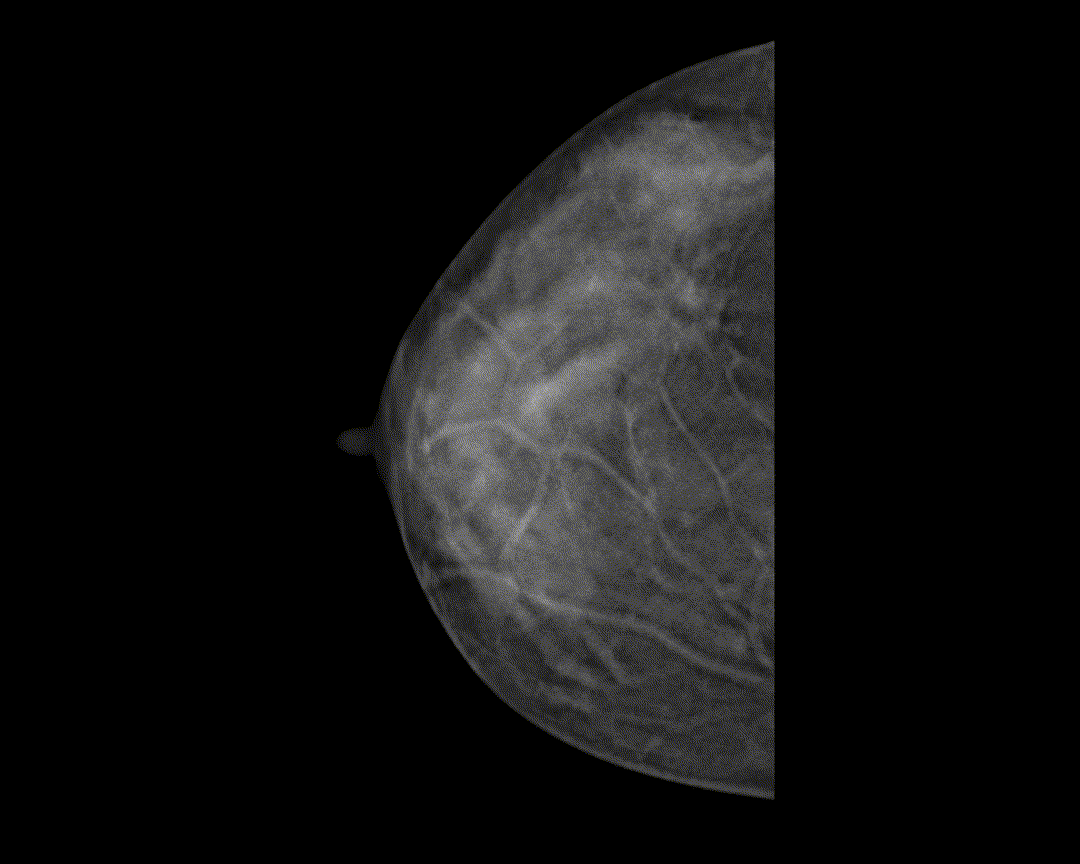

智能病灶定位*

快速在同一体位不同图像类型中精准定位感兴趣可疑区域,缩短阅片时间,提高效率。